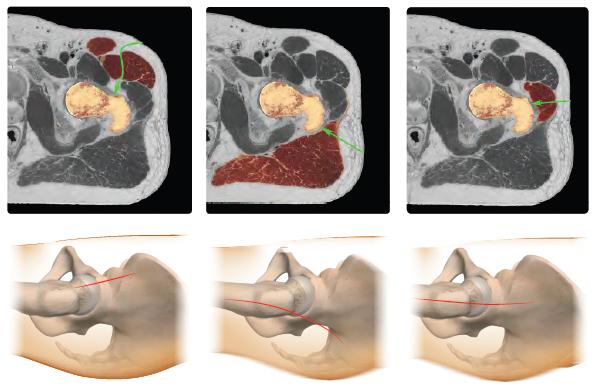

Nelle artrosi post-traumatiche uno studio preoperatorio con TC ha reso possibile l'impianto di protesi standard non cementate rimuovendo solo i mezzi di sintesi che potevano impedirne l’utilizzo, cosí da ridurre l’esposizione e i tempi chirurgici e ridurre l’invasività ed il sanguinamento di queste complesse procedure chirurgiche. A seconda dell’età e della corporatura del paziente è stato scelto l’approccio chirurgico meno invasivo, per diminuire l’incidenza di complicanze e la necessità di trasfusioni. Su un totale di 235 anche, 106 (45%) sono state operate tramite accesso mini-invasivo anteriore, l'incisione può essere longitudinale o trasversa a "bikini", sulla piega della coscia in modo da rimane nascosta dagli slip. Sui piani profondi, sfruttando l’interstizio esistente tra il muscolo tensore della fascia lata ed il sartorio, questo accesso permette di giungere all’articolazione dell'anca ed impiantare la protesi senza disinserire alcun muscolo. L'intervento per via anteriore può essere eseguito in maniera convenzionale, oppure con un letto operatorio dedicato con cui è possibile manovrare l'arto operato dall'esterno. Il video dell'accesso anteriore mini-invasivo è stato inserito nel percorso formativo di aggiornamento dei chirurghi ortopedici americani dell’American Academy of Orthopaedic Surgeons del 2014 (Orthoportal Multimedial Library).

L'accesso mini-invasivo postero-laterale, è stato utilizzato in 115 pazienti su 235 (49%). Questo accesso permette di raggiungere l’articolazione sacrificando solo alcuni muscoli extrarotatori dell’anca, dalla scarsa valenza funzionale. Questa via di accesso è ideale perché consente un'ampia esposizione specie nei complessi casi di grave deformità come esito di patologie congenite dell’anca, ma allo stesso tempo favorisce una rapida riabilitazione, in quanto la muscolatura glutea non viene disinserita. Il video dell'accesso postero laterale mini-invasivo è stato premiato all'American Academy of Orthopaedic Surgeons del 2014 come miglior contributo scientifico dell’anno. Inoltre è stato inserito nel percorso formativo di aggiornamento dei chirurghi ortopedici americani dell’AAOS (Orthoportal Multimedial Library).